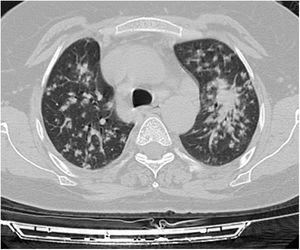

A relationship was identified between the pleura and one or more of the lesions in 25 of the 34 patients diagnosed with PAE (73.5%) (Fig. 1). Following the lesion-pleura relationship, multiple lesions were uniformly scattered throughout the bilateral lung parenchyma in 19 patients (55.8%), seven patients (20.6%) presented with a solitary pulmonary lesion and three patients (8.8%) had multiple unilateral lesions. The diameter of one or more lesions was greater than 3cm in 11 patients (32.4%), only three patients (8.8%) had conglomerated lesions (Fig. 2) and seven patients (20.6%) showed cavitization in some of the lesions. The majority of cavitary mass measured greater than 3cm (Fig. 3). Calcified lesions were recorded in five patients (14.7%), and some of the calcified lesions with lobulated contours had a typical popcorn appearance. Lobulated contours were observed in a significant proportion of non-calcified lesions. Some of the lesions had irregular contours and spicular extensions mimicking malignant processes in five patients (14.7%), while three patients (8.8%) showed multiple micronodular densities with a bilateral uniform dispersion pattern (Fig. 4). The appearance of pulmonary involvement resembled miliary tuberculosis. Parenchymal lesions were accompanied by pleural effusion and parenchymal consolidation in only three patients (8.8%) (Table 1).

Small nodules in the liver and lung parenchyma are asymptomatic, and the disease may be detected incidentally on ultrasound, CT or MRI performed for other reasons. USG and CT reveal central necrosis, calcifications, irregular contours, and heterogeneous and hypodense foci. MRI is superior in the identification of central necrosis, however, this method does not serve well in the differential diagnosis of calcifications and small lesions. Positron emission tomography-computed tomography (PET-CT) is an important method for detecting the extent of the disease in the body and disease recurrence, and in identifying the viability of the parasite. Imaging studies often show findings that are suspicious for carcinoma or sarcoma. The general medical condition of patients with AE is better than those with suspected malignancy, as was the case in the present study.9 The most common pulmonary findings of CT scans of patients were a relationship with the pleura (73.5%), a bilateral uniform dispersion pattern (55.8%), the presence of a lesion with lobulated contours (35.3%) and the presence of a mass measuring greater than 3cm (32.4%). The lesion showed spicular extensions in 14.7% of the patients, mimicking malignancy.